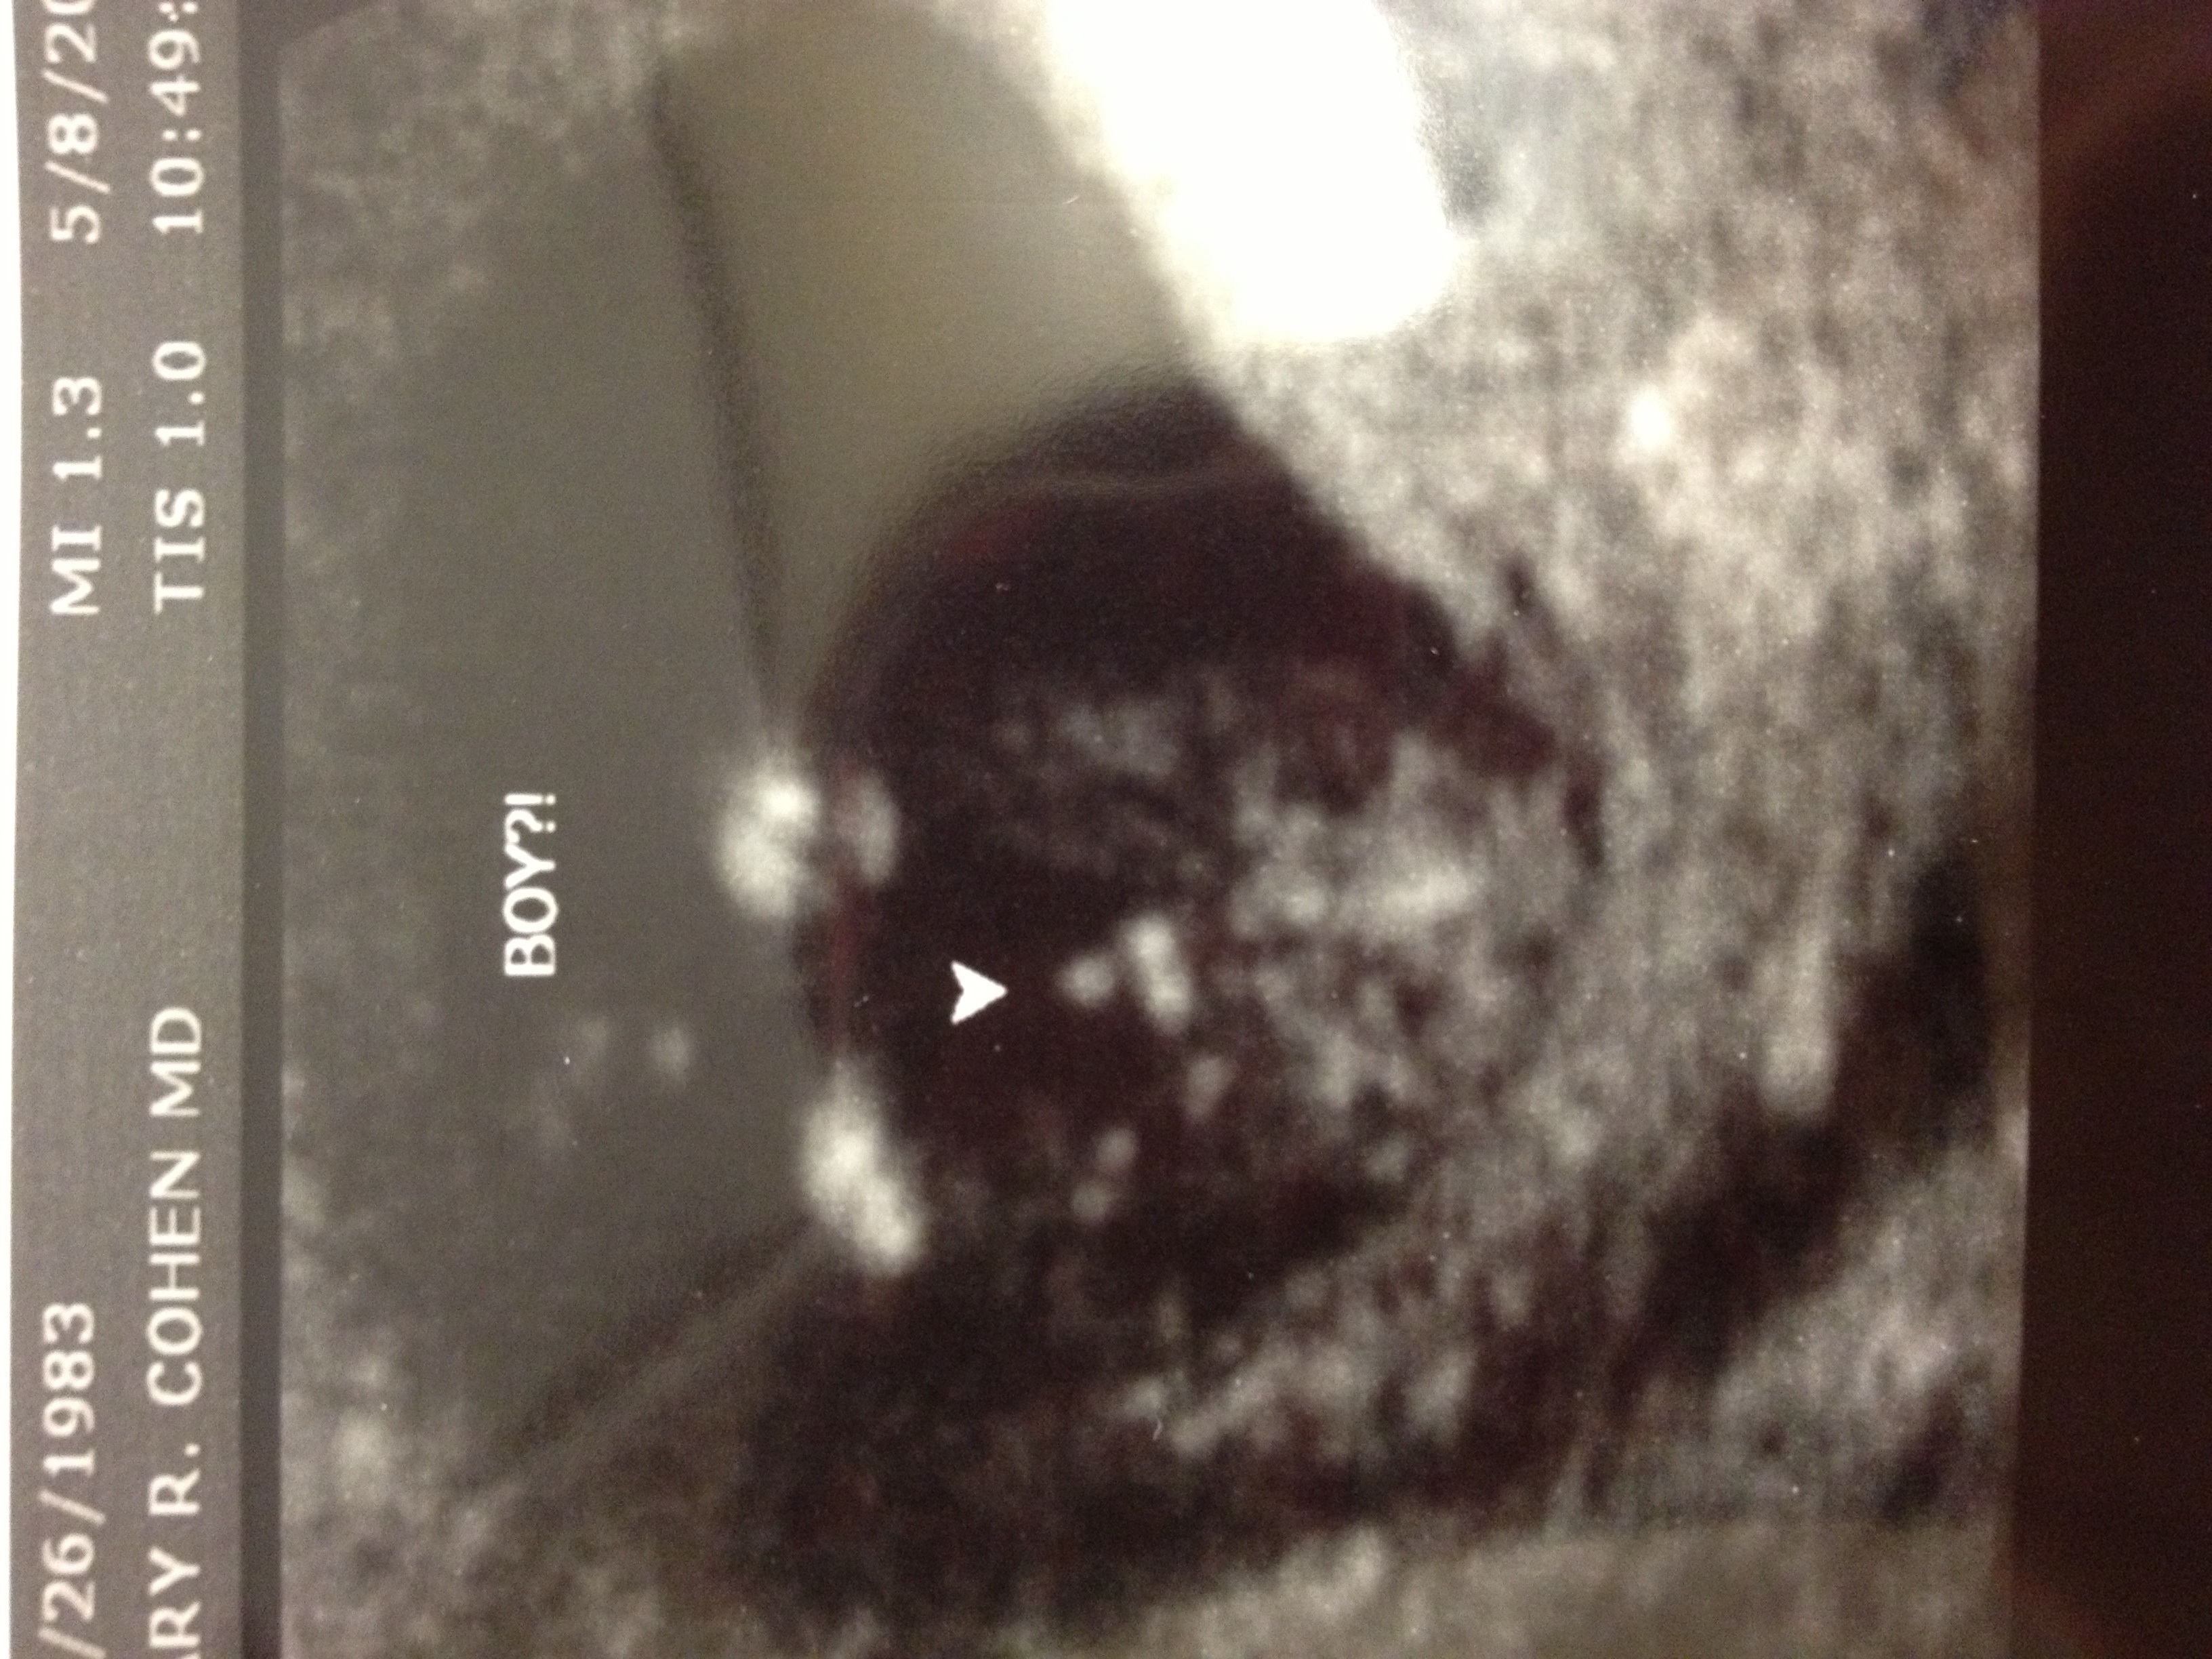

The first pic is a potty shot, the second shows the nub. I was either 12 w, 3 days or 13 w, 1 d. The experienced tech seemed confident it's a boy.

That def. looks boy!!! I can see the marbles and everything on the potty shot! lol I was told boy also by my tech with DS3!! SO COngrats on your long awaited baby boy!!! :)